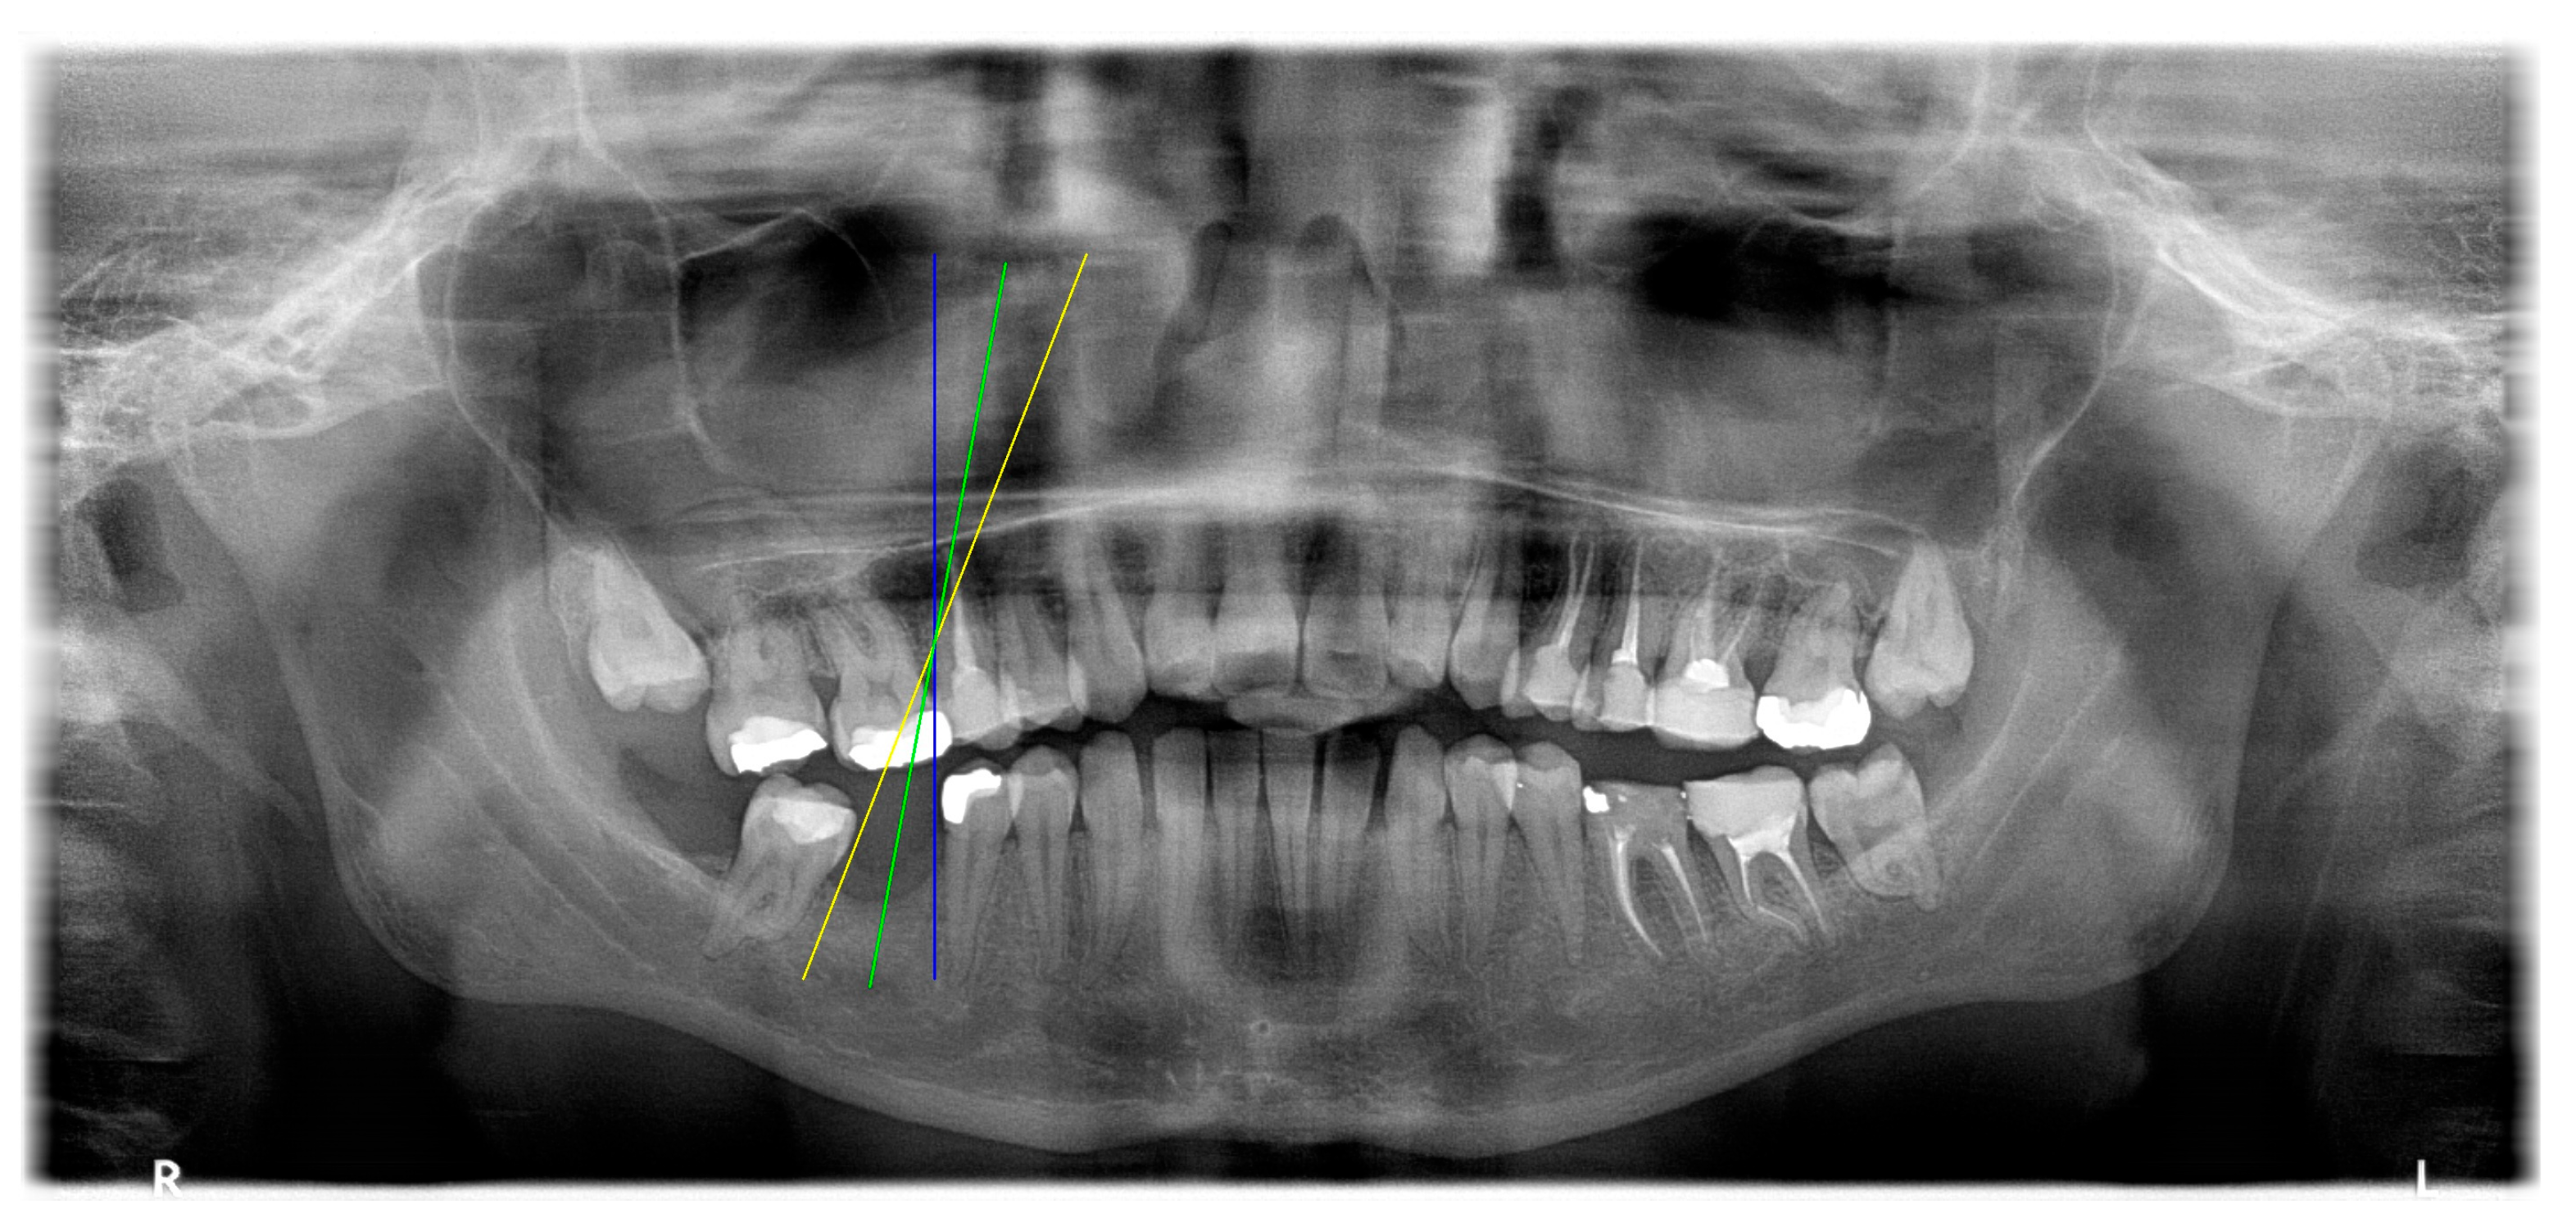

The angle bisector of the two auxiliary lines was then calculated using the angle bisector formula shown in (8), where (, , ) and (, , ) represent the coefficients of the two lines. The resulting internal angle bisector defines the preliminary implant pathway orientation derived by this framework. This bisector represents the most stable implant pathway orientation direction, ensuring that the implant avoids adjacent teeth and critical anatomical structures while maximizing bone–implant contact area. Such orientation enhances osseointegration stability and prevents complications from improper angulation, such as malocclusion or uneven stress distribution. The visualization of this process and the algorithmic design are presented in Figure 8. Finally, the auxiliary pathway generated by the algorithm was compared and overlapped with the implant pathway orientation annotated by dentists on the images to evaluate the predictive capability and accuracy of the model. The overlap results serve as a basis for further model optimization and provide valuable reference information for clinical application.

Figure 8.

Auxiliary lines are derived from adjacent teeth, the blue and yellow line is the result of implant pathway orientation visualization algorithm, and the green is the best implant pathway orientation.

3.3. Comparison with Clinical Ground Truth and AI-Assisted Framework

This subsection presents a comparison between the dentist-defined clinical gold standard and the predictions generated by our AI-assisted framework to evaluate the reliability of implant pathway orientation. The result is shown in Table 10, the preserved DPR validation set was used for verification, and the AI-assisted framework results were overlaid onto the original DPR images to provide a clear visualization. The AI-assisted framework pathways (green lines) were highly consistent with the dentists’ ground-truth annotations (black lines). Quantitatively, the mean squared error (MSE) between the predicted implant direction and the dentists’ planned results was only 1.537° across multiple test images. This minimal deviation validates the proposed system’s technical feasibility. It highlights its clinical potential to provide accurate and stable guidance for implant placement, thereby reducing the risk of misalignment and supporting efficient preoperative orientation.